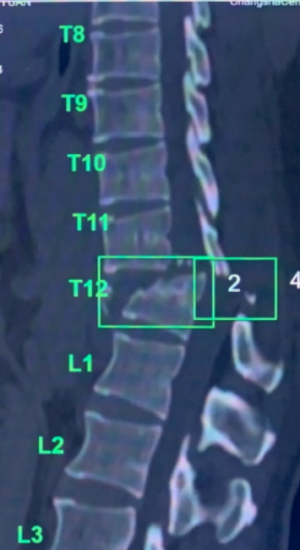

)急诊科,CT和磁共振检查提示胸腰段T11、T12椎体爆裂性骨折并脱位,并脊髓损伤伴截瘫,这是脊柱脊髓损伤中最严重的情况。

术前检查示胸腰段T11、T12椎体爆裂性骨折并脱位